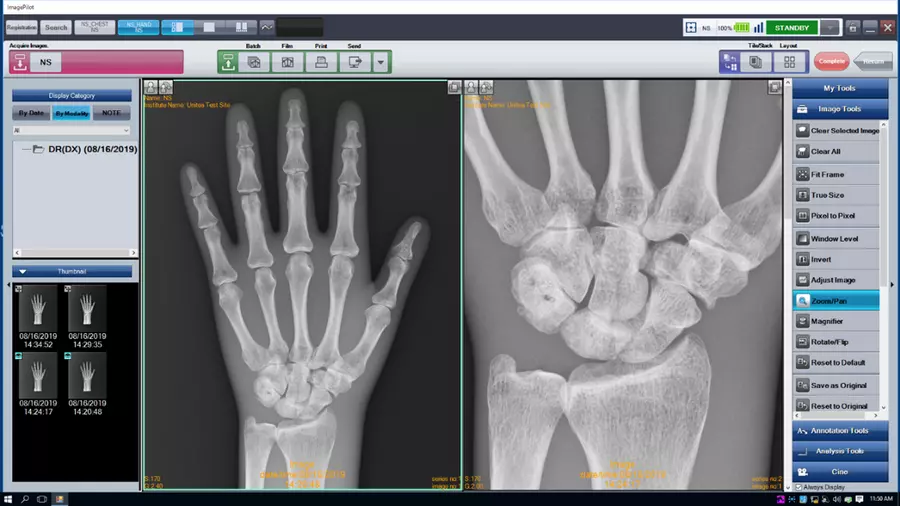

- ImagePilot: Всё в одном

Регистрация + Получение снимка + Просмотр + Измерения + miniPACS

ImagePilot: Всё в одном Простая регистрация пациента, быстрый просмотр и описание, множество инструментов для измерений и обработки снимков, мини-PACS для хранения данных, различные опции вывода и печати